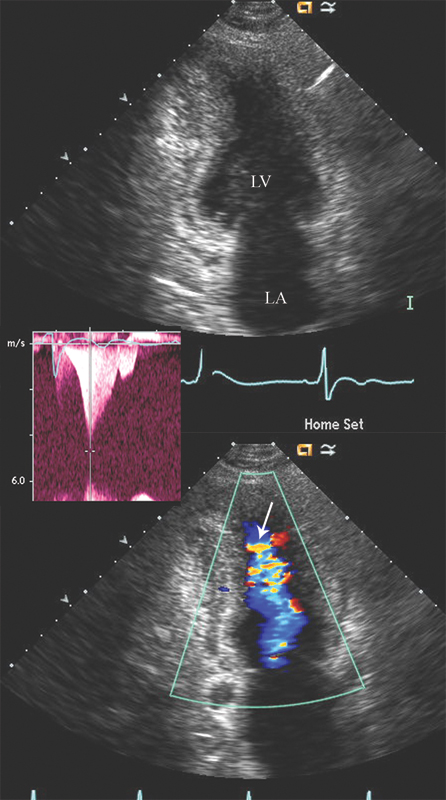

فحوصات تشخيصية لبعض امراض القلب والشرايين التاجية